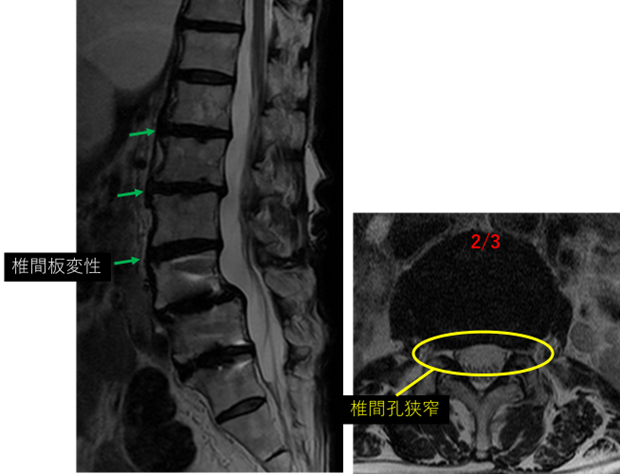

画像及び所見について

L1/2: 椎間板変性

L2/3: 椎間板変性、膨隆、左椎間孔狭窄

L3/4: 椎間板変性

L4/5: 術後

L5/S: 術後

以上の事が画像上認められます。

L1/2、2/3、3/4 に

椎間板変性、膨隆、左椎間孔狭窄 を認め、主症状の原因の可能性が高い。